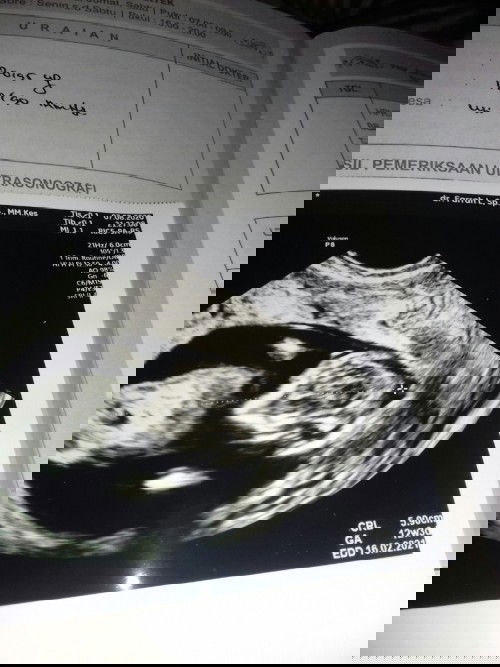

Sedih sih rasanya di tes positip di usg juga ada, tapi knapa keluaran darah tiap pagi😭kata dok debay nya shat.. Tapi wktu itu saya gx hed 1thn sesudh di lepas kb yg 3bln sekali,udh msuk 2thn aq lepas terus aq minum fil 3bln krna aq pingin hed nya lancar..terus disitu udh stop hed smpai skrng aq sllu tes tiap bln hasilnya negatip, terus bagian bln juni aq tes karna aq sakit hasil ny postip,terus begitu aq periksa ke bidan,kata bidan di usg aj soalnya blm tau hpl nya,soalny gx terakhir hed nya.. terus wktu itu aq kena pendarahan kaya kegguran, terus aq usg 4D soalnya pingin keliatan gitu apakah ada janin apakah engga. Pas usg janin ada udh masuk 13week, kata dok debay nya shat cuma ada pendarahan doang, dok saran jangan hb sama jgn aktipitas dlu soalnya kndungan ku lemah😭mau tanya ini pendarahan darh yg 1thn apa gimna aq sedih sih#Nanya #jangandibully ank yg ke 3

Minggu kemrin sya pendarahan, tapi alhamdulillah di usg bayi nya sehat